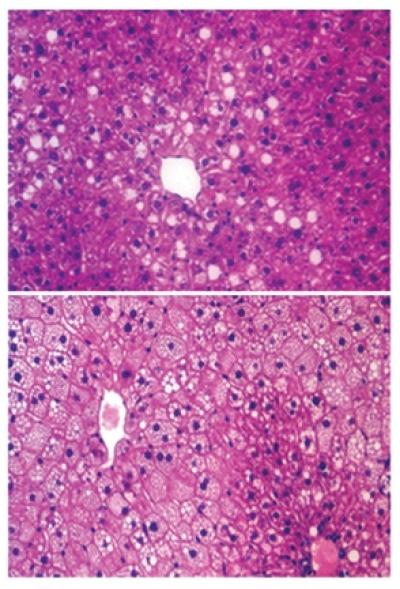

Las células de alto grado en grasas-inducidos por la dieta hígados grasos en ratones de tipo salvaje se caracteriza por las gotas de lípidos más grandes, pero específicos de hígado en ratones knock-out HDAC3 una dieta alta en grasas se caracteriza por pequeñas gotas de lípidos, aunque el contenido de lípidos totales aumentaron en comparación con los ratones de tipo salvaje.